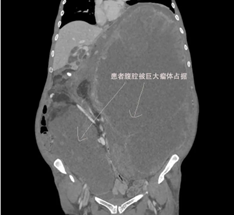

平滑肌肉瘤是一种起源于平滑肌细胞的罕见恶性肿瘤,侵袭性强、易复发转移。2022年,吴女士因腹部肿物在外院首次手术。同年肿瘤复发,辗转多地后,她找到北京协和医院基本外科王维斌主任进行第二次手术,切下了重逾30斤的平滑肌肉瘤。尽管术后进行了积极化疗与靶向治疗,但未遏制住平滑肌肉瘤的持续进展,到2025年10月,吴女士腹腔内的瘤体最大径已达32.5cm,让她腹部胀痛、无法平卧,连呼吸都十分困难。

在基本外科大查房时,医护人员针对吴女士的病情深入讨论,最终达成一致共识:结合患者腹部触诊柔软、影像学检查未见明确远处转移的临床特征,可尝试通过手术探查完整切除肿瘤。这意味着,吴女士还有通过手术得到减瘤治疗的机会。